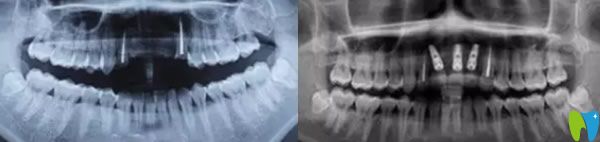

郝醫(yī)生通過醫(yī)學(xué)種植技術(shù),根據(jù)老公牙齒狀況設(shè)計(jì)種植方案。他將種植體與人體兼容性高的鈦金屬精準(zhǔn)植入缺牙區(qū)的牙槽骨內(nèi),等三個月后,人工牙和牙槽骨緊密結(jié)合,再做烤瓷牙、全瓷牙冠。郝醫(yī)生植入牙根手術(shù)完成后,老公從手術(shù)室出來牙齦看著就沒有之前那么憋了,飽滿了許多。

三個月后,我們又來到成都瑞爾口腔,醫(yī)生說恢復(fù)的很不錯,牙槽骨和種植體已經(jīng)緊密結(jié)合,可以安裝基臺,戴上牙冠后,牙齒咀嚼功能恢復(fù)了,可承受正常的咀嚼力量,美觀上幾乎和自然牙一樣。郝亦工醫(yī)生建議后期一定要保持好口腔衛(wèi)生健康,細(xì)心呵護(hù),這樣能夠保證種植牙的使用壽命。